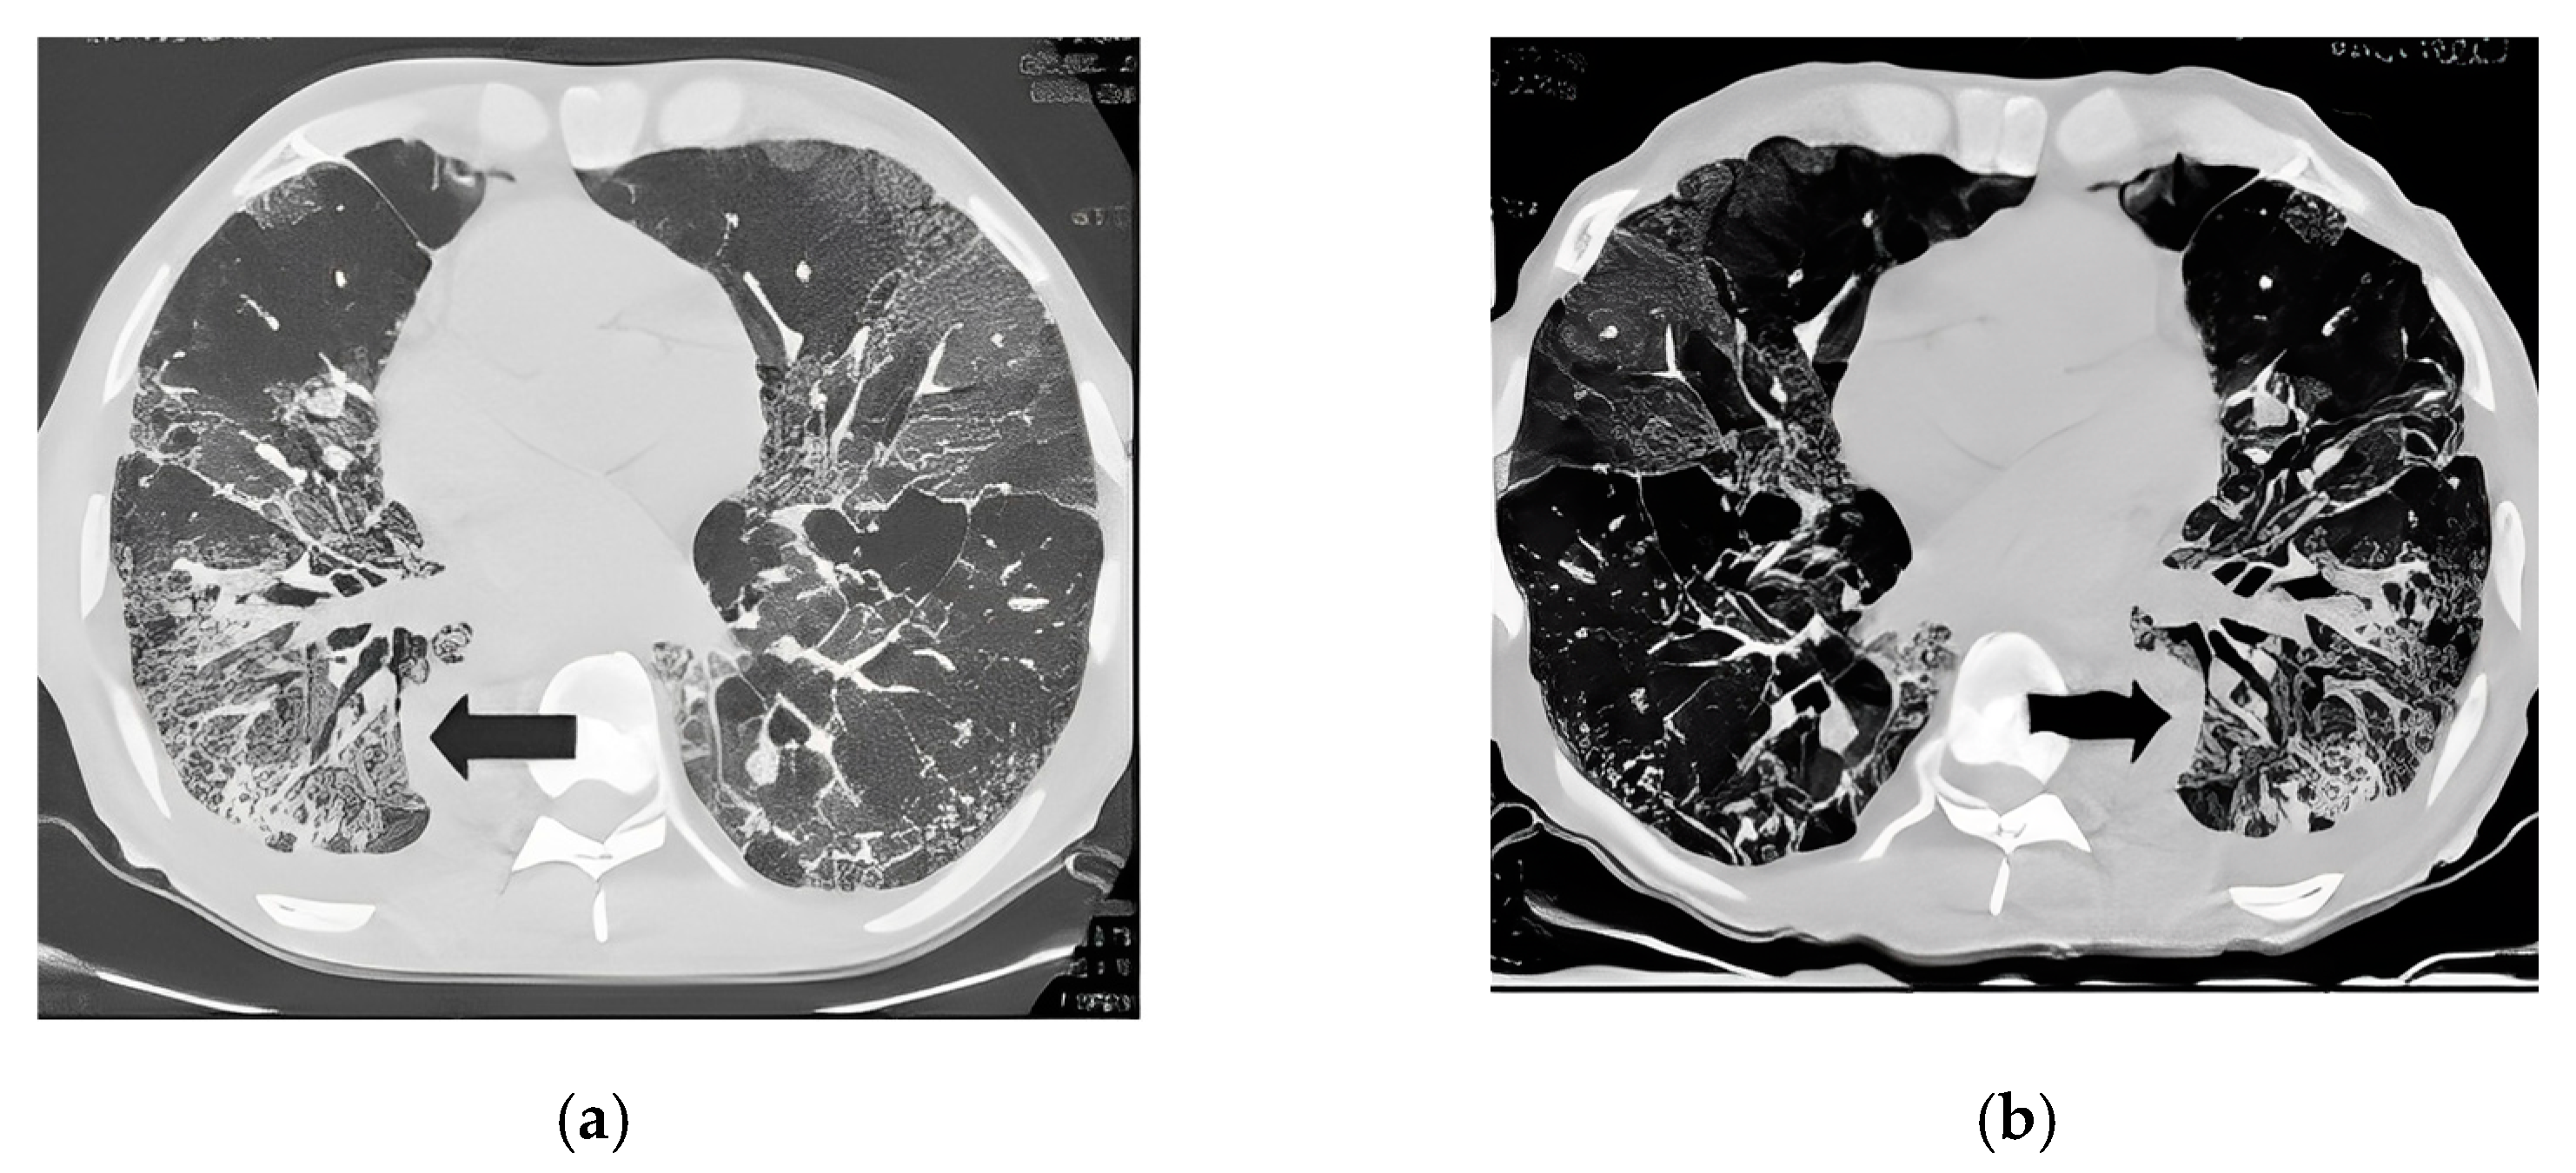

2.3.1. Lung Segmentation

2.3.2. Infection Area Segmentation

2.3.3. Segmentation of GGO and Consolidation Patches